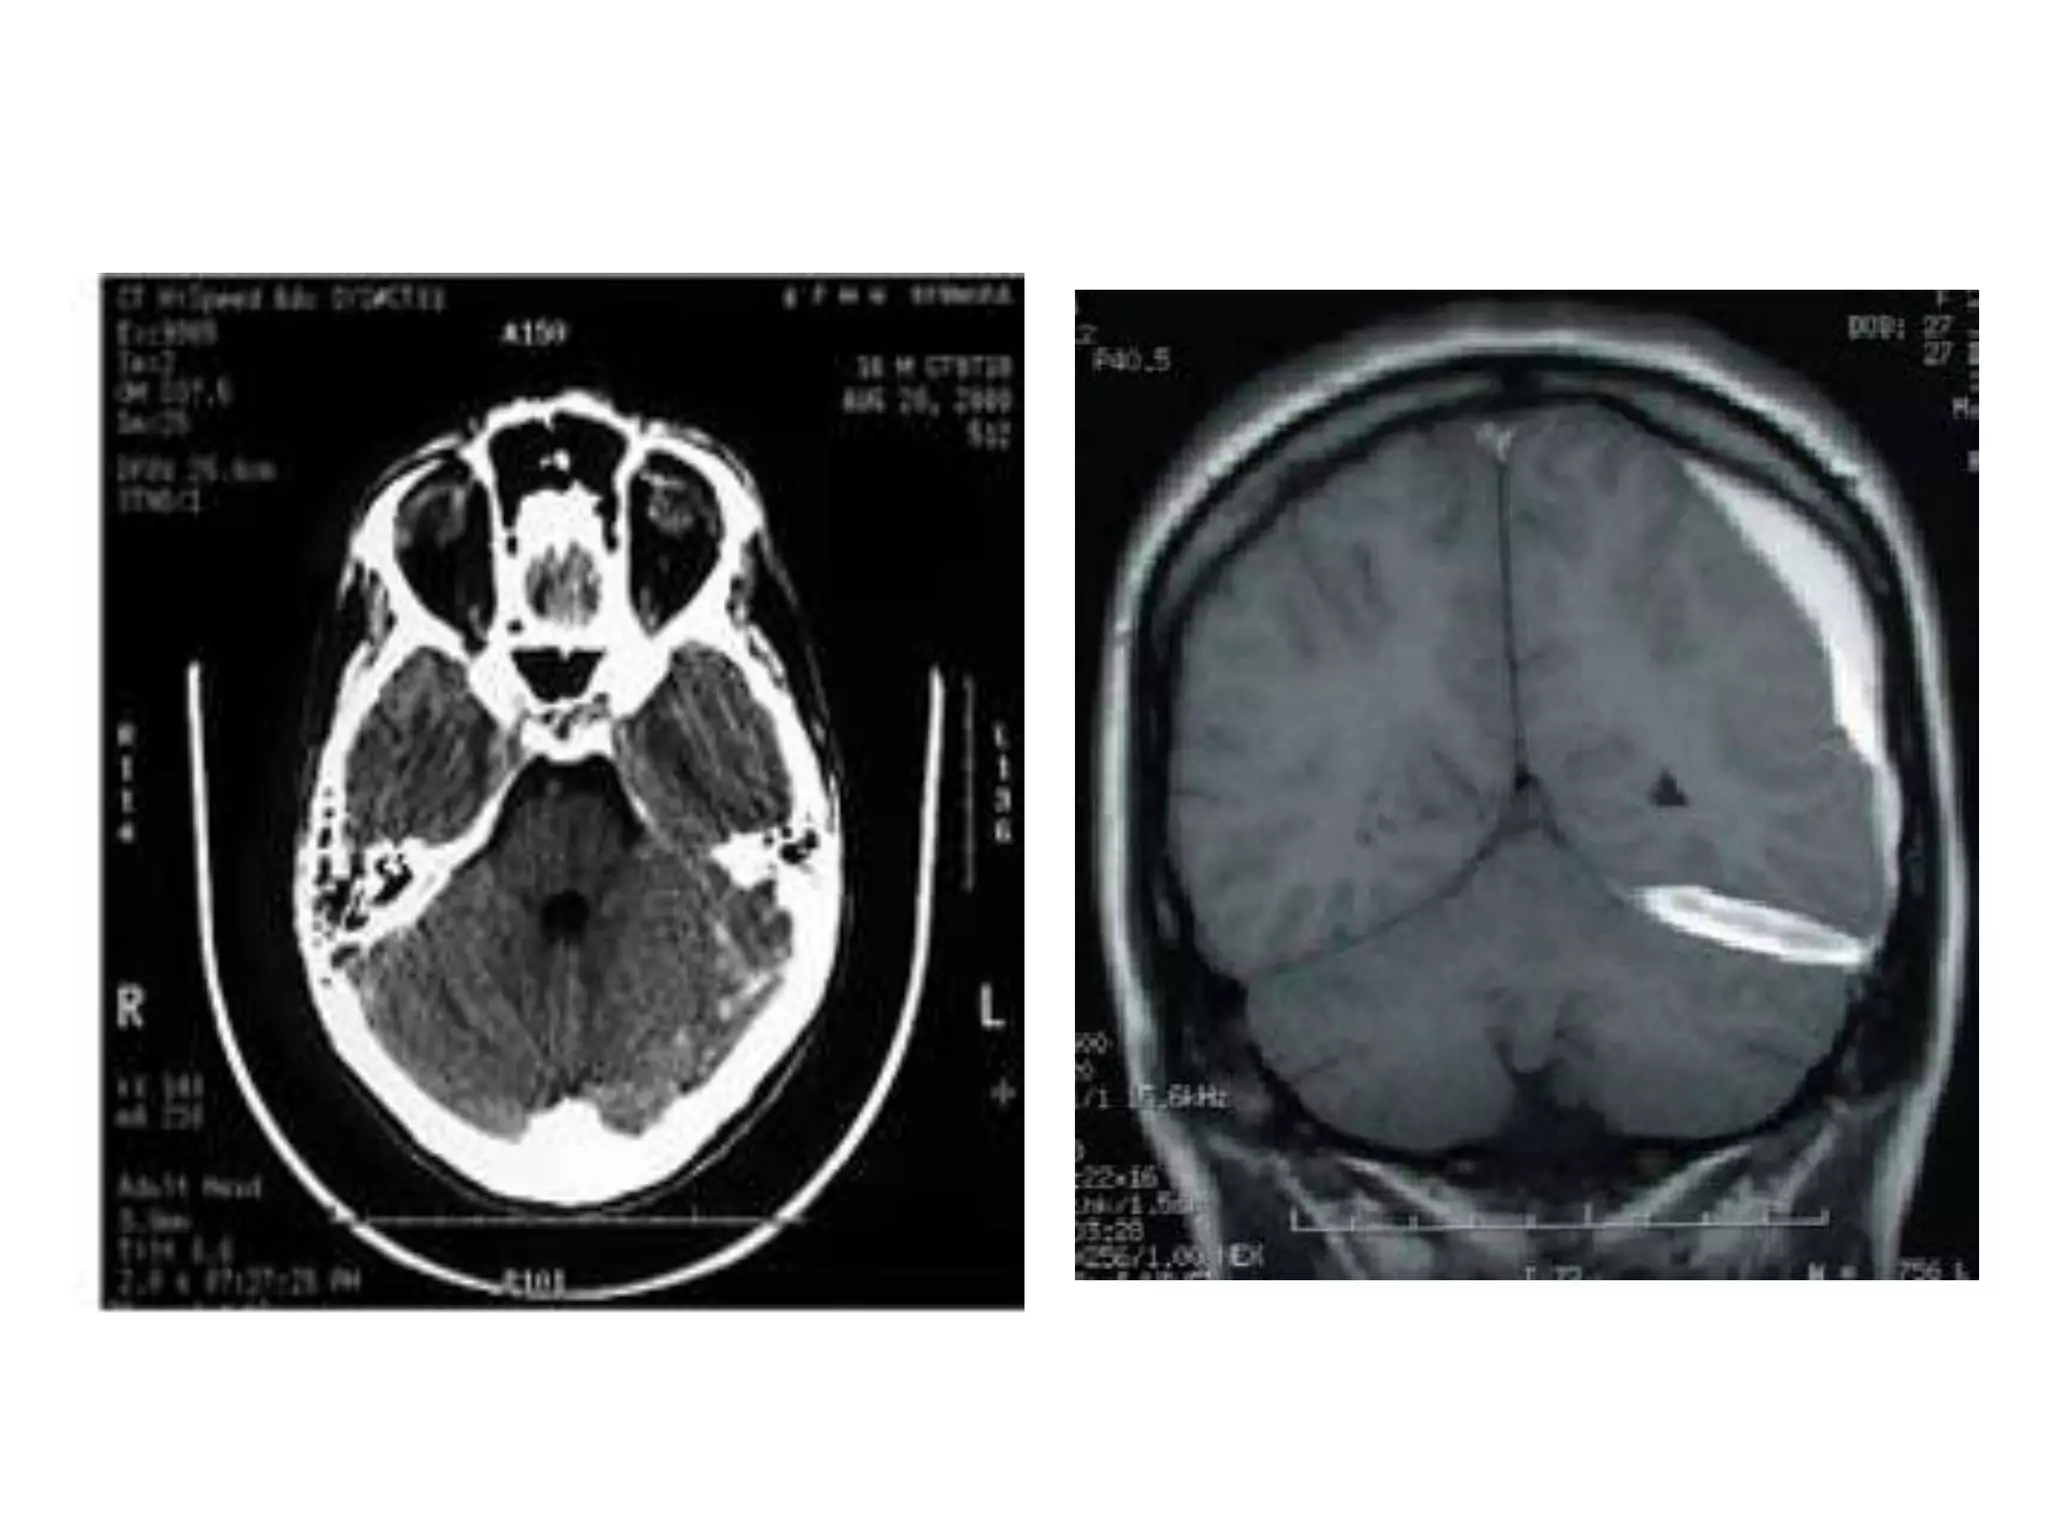

• On axial CT , structures medial to line of tentorial

edge are infratentorial and those lateral are

supratentorial.

• Anatomy of cerebral hemispheres and mid brain – T1 W

MRI.

• Internal grey - white matter areas – T2 W MRI.

• Saggital and Coronal T1 weighted MRI – accurate

assessment of ventricles and C. callosum

• Mid Saggital section – for shape and configuration

of Aqueduct of Sylvius.